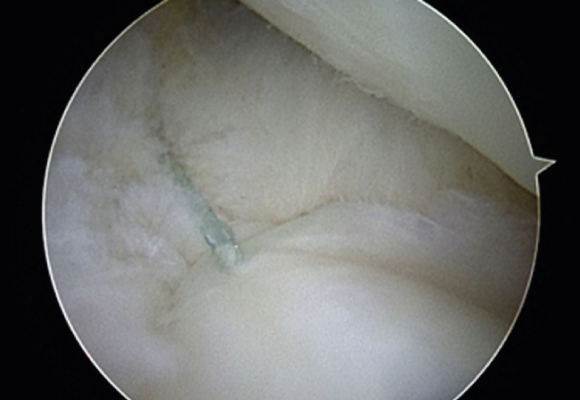

연골판봉합술

혈관이 있는 부위에 파열이 발생한 경우 연골판을 봉합해 주는 수술 시행

ㆍ환자 동의를 받은 자료이며, 이미지 사진은 실물과 다를 수 있습니다. (22.06.09)